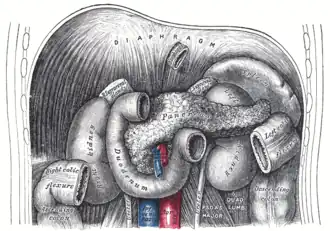

The duodenum and jejunum depicted in situ. The suspensory muscle of the duodenum connects posteriorly to the duodenojejunal flexure, behind the pancreas, shown. | |